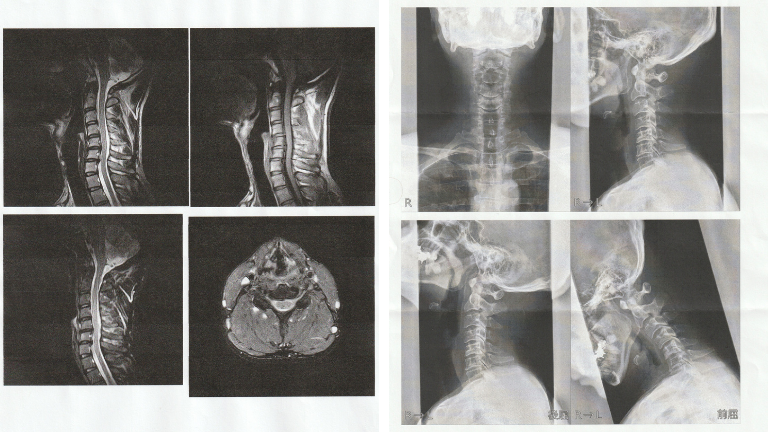

MRIデータとレントゲンで

より安心な施術を提供

首のヘルニアや狭窄症、ストレートネックと病院で言われた方の多くはMRIやレントゲンの検査を必ず受けています。整体院omoではその画像検査をご持参いただき、施術の判断材料として使います。

また、撮影の時期が古い場合には提携しているMRI施設のある病院に紹介状を作り予約もこちらで取ることが可能です。

首ヘルニア・ストレートネックのMRI・レントゲン

左:MRI検査データ 右:レントゲン画像

病院のMRIデータやレントゲンは必要ですか?

撮影された場合はご持参をお願いしております。病院に問い合わせていただければCDデータとして貰えることが多いです。

整体の効果向上にもつながりますので、ご協力のほどお願いいたします。